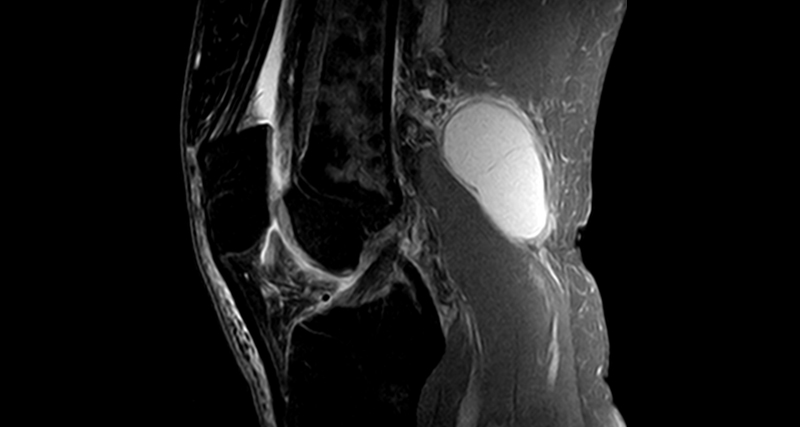

- MRI (Magnetic Resonance Imaging)

- Offers a more detailed view of the joint structure and can identify any meniscus tears, cartilage damage, or inflammation.

- Particularly useful when a Baker’s cyst is linked to complex joint conditions.